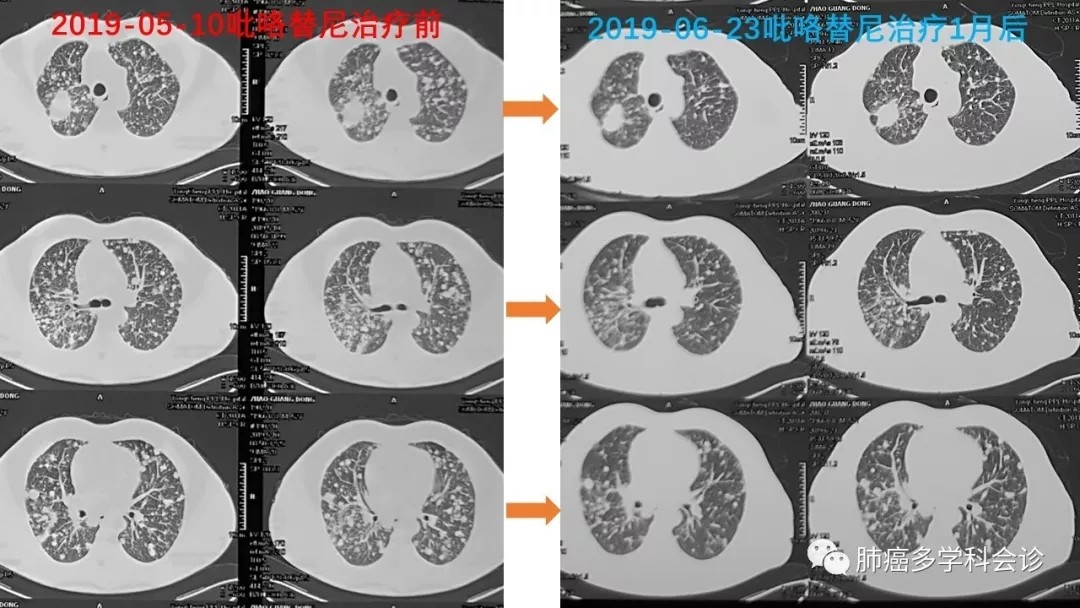

患者口服吡咯替尼后不久即感觉呼吸改善症状明显减轻,治疗一个月以后复查CT显示两肺弥漫的小转移灶缩小或消失: